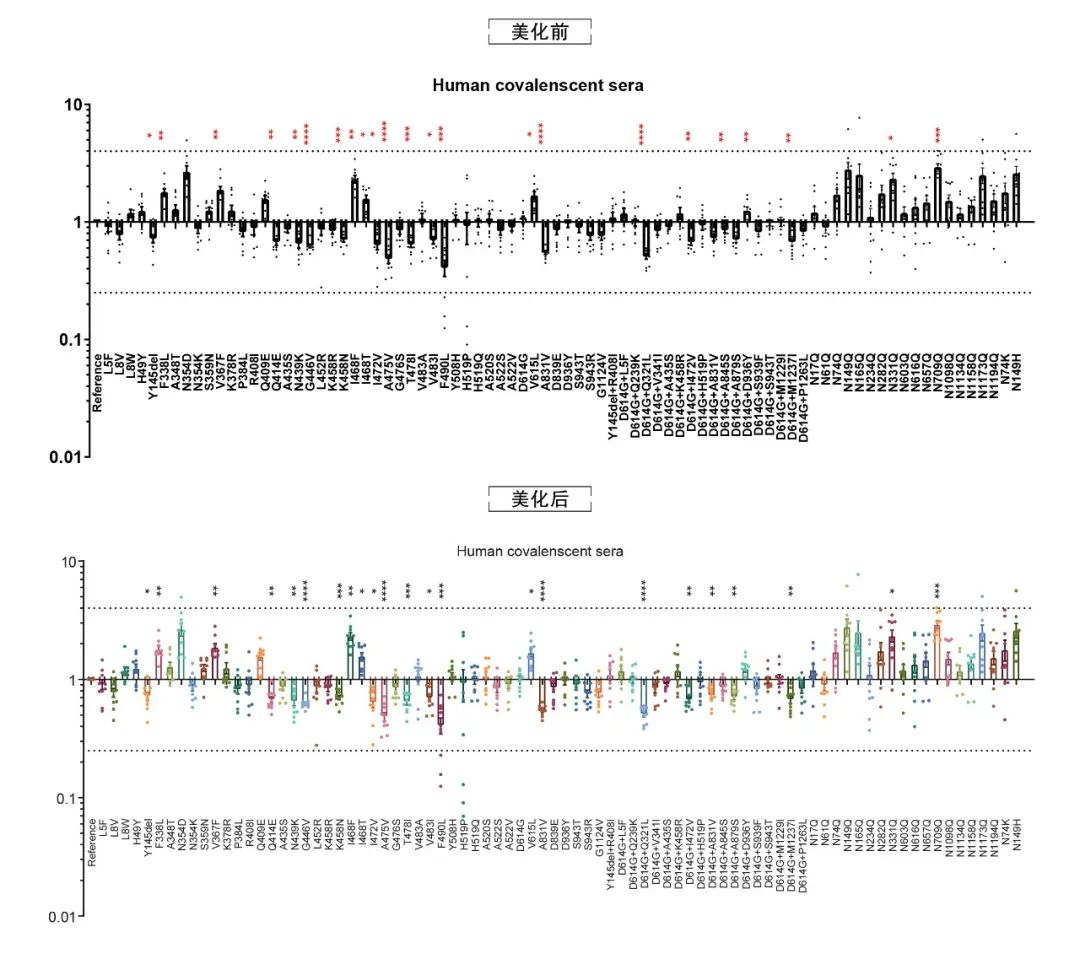

论文图表美化

滑动查看更多 点击查看大图